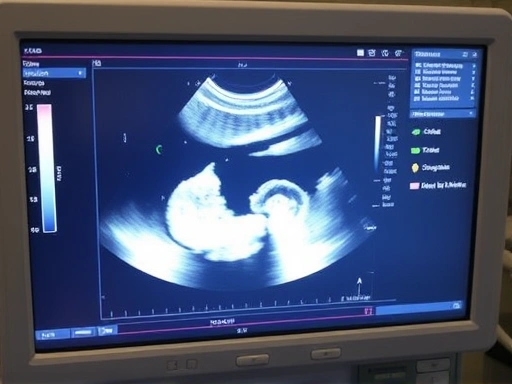

초음파 (Ultrasound)를 통한 태아 성별 확인 시기

초음파 검사는 임신 중 태아의 건강 상태와 성장을 확인하는 가장 보편적이고 안전한 방법입니다. 성별 확인 역시 초음파를 통해 이루어지는데, 대략 임신 12주 이후부터 생식기 발달이 시작되어 이론적으로는 성별 구분이 가능해집니다. 그러나 이 시기에는 아직 태아의 크기가 작고 자세에 따라 생식기가 명확하게 보이지 않을 수 있어 정확도가 상대적으로 낮을 수 있습니다.

대부분의 의료기관에서 성별을 명확하게 확인하기에 가장 적절한 시기는 임신 16주 이후입니다. 이 시기부터는 태아의 생식기가 충분히 발달하여 남자아이의 경우 고환과 음경, 여자아이의 경우 음순이 명확하게 구분되기 시작합니다. 숙련된 초음파 기사나 의사의 경우, 태아의 자세가 좋다면 16주 이후의 초음파 검사에서 비교적 높은 정확도로 성별을 예측할 수 있습니다.

하지만 태아의 위치, 양수의 양, 임산부의 체형 등 여러 요인에 따라 성별 확인이 어려울 수도 있습니다. 간혹 아기가 다리를 꼬고 있거나 손으로 가리고 있어 성별 부위를 가릴 경우, 한 번의 검사만으로는 성별을 정확히 알기 어려울 수 있습니다. 이럴 때는 다음 정기 검진 시 다시 확인을 시도하거나, 다른 각도에서 재검사를 진행하기도 합니다.

고해상도 의료용 초음파 기기 화면에 태아의 모습이 선명하게 비치고 있으며, 성별을 암시하는 특정 부분이 클로즈업되어 있는 모습, 정확하고 신뢰성 있는 태아성별확인 정보가 담긴 이미지를 연상시키는 정교하고 전문적인 묘사